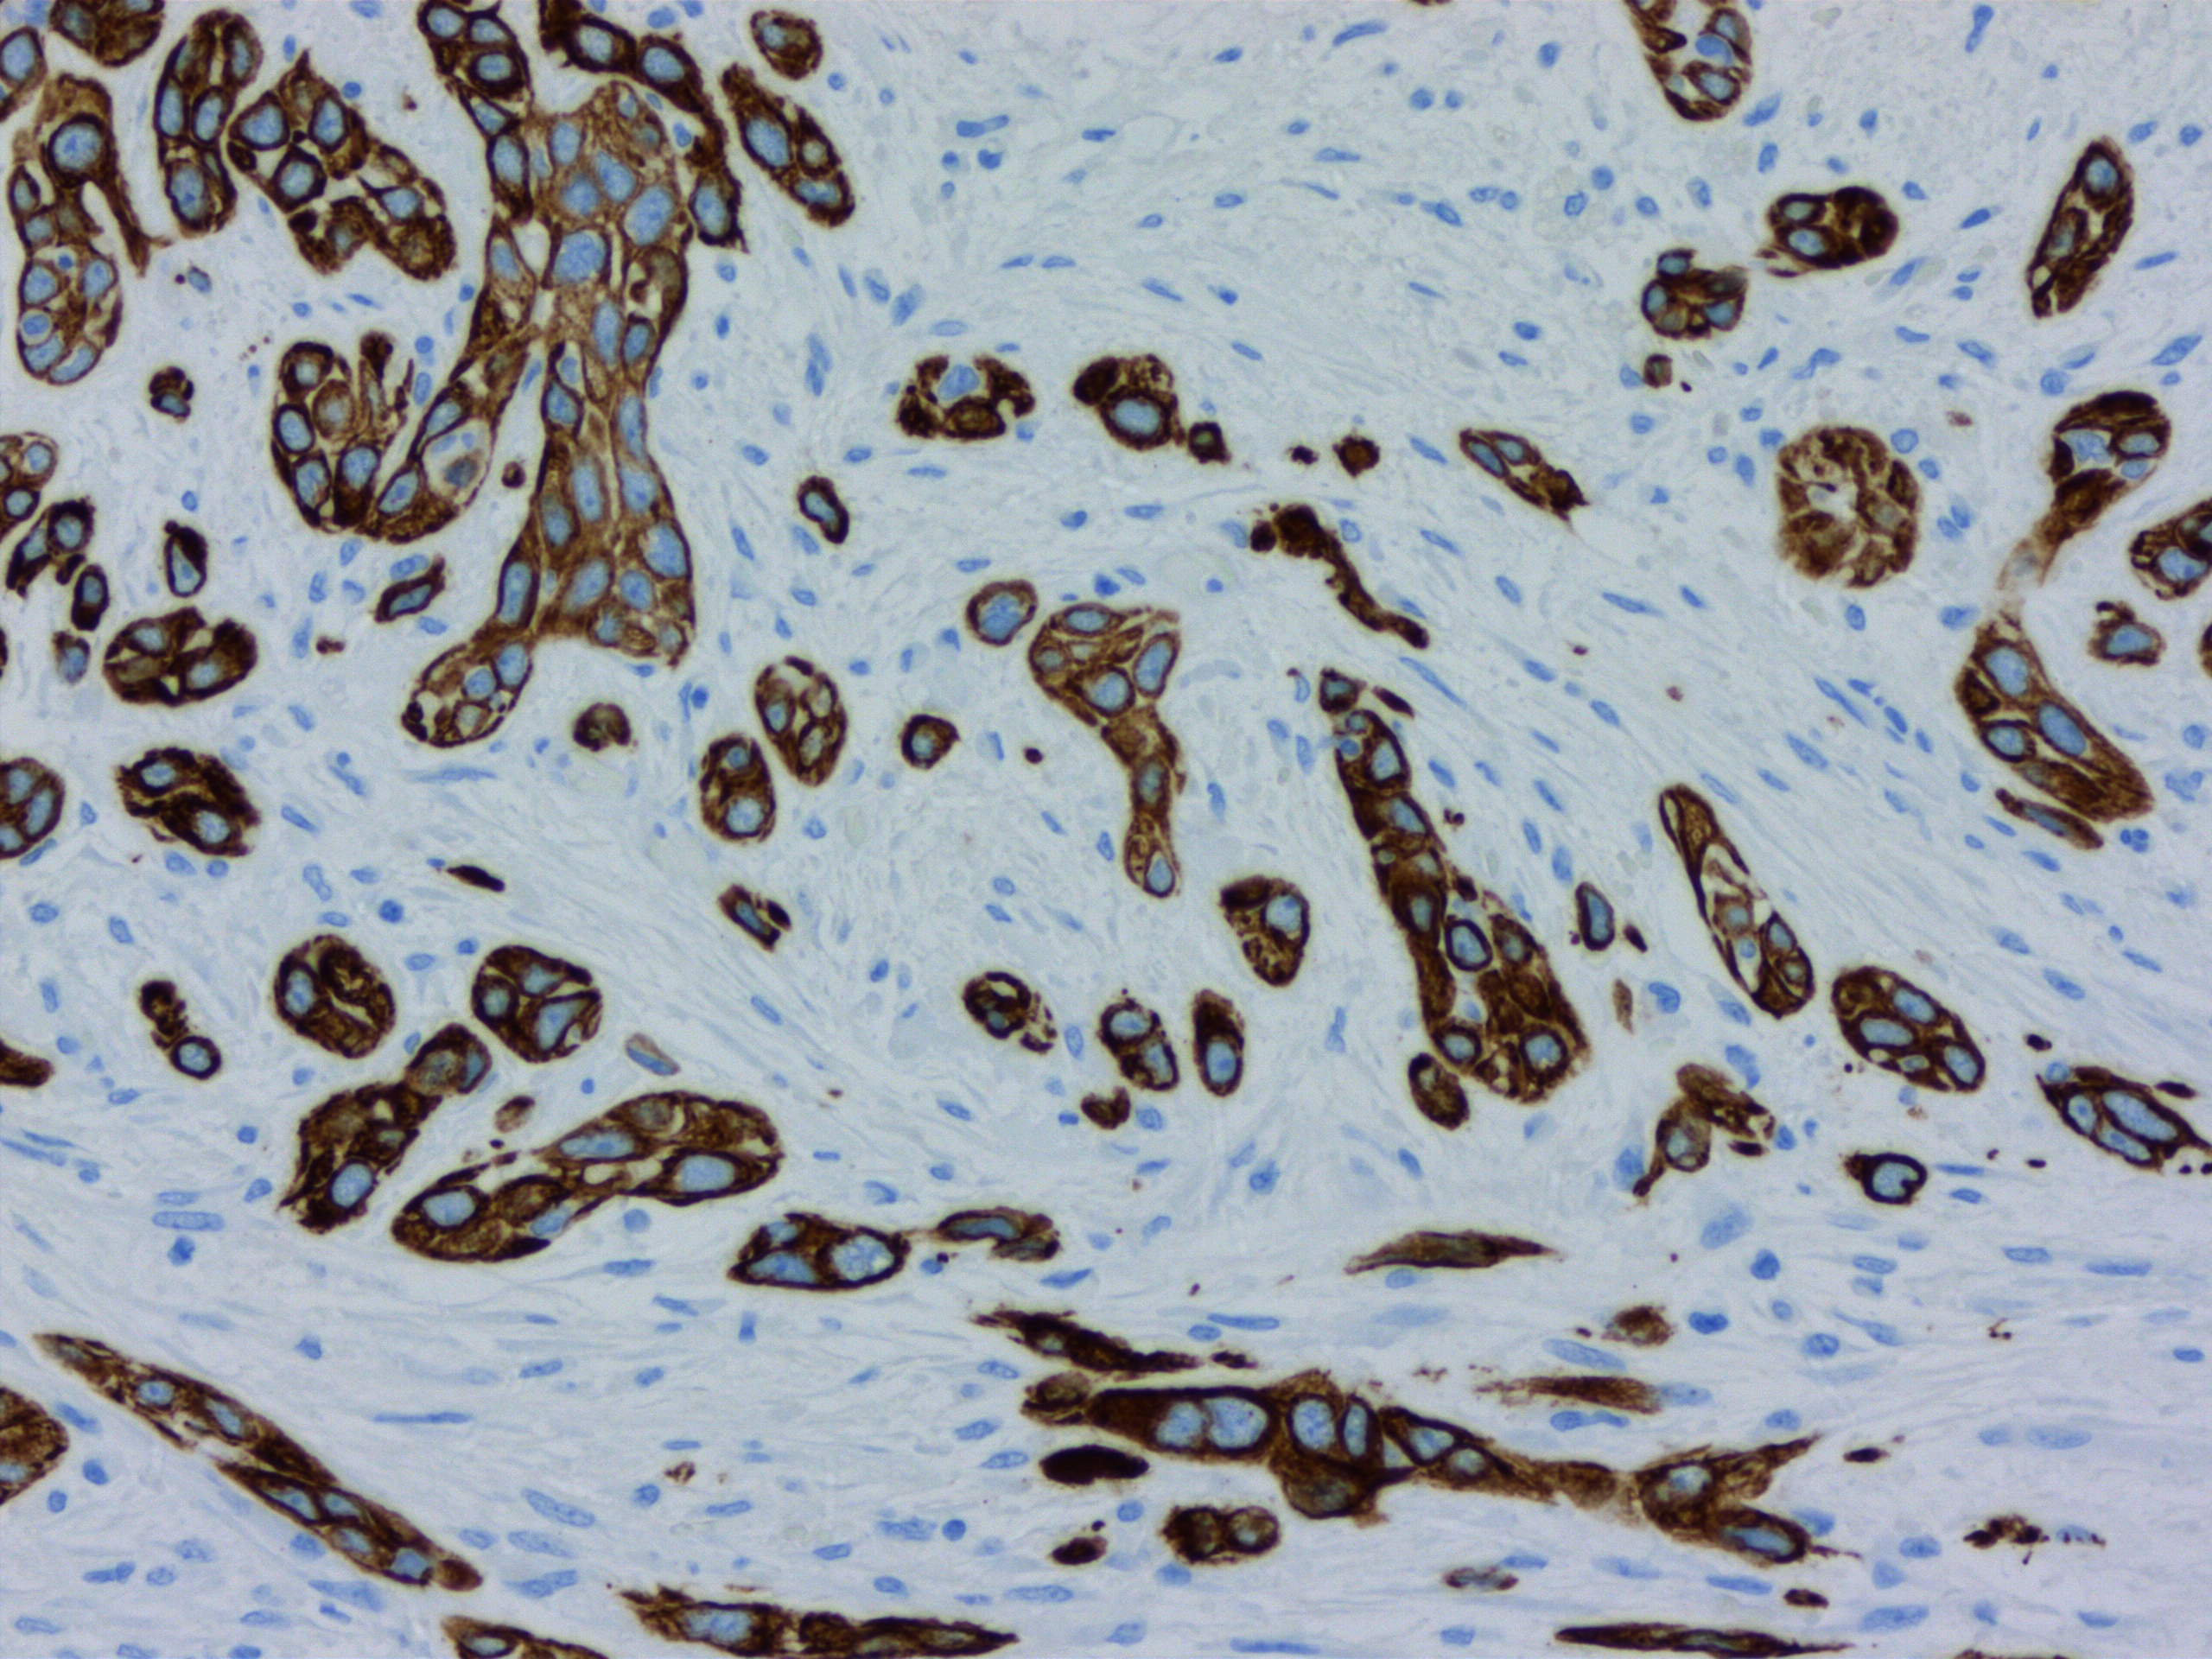

Stuttgart, 23. März 2023 – Bauchspeicheldrüsenkrebs gehört nach wie vor zu den tödlichsten Krebsarten überhaupt. In Deutschland werden dieses Jahr voraussichtlich rund 21.000 Menschen die Diagnose erhalten. Davon erliegt die Hälfte innerhalb des ersten halben Jahres der Krankheit, nur zehn Prozent überleben fünf Jahre. Neben der späten Diagnose ist eine der größten Hürden bei der Behandlung von Bauchspeicheldrüsenkrebs die erstaunliche und einzigartige Fähigkeit der Tumorzellen, sich der Behandlung zu widersetzen, indem sie ihre molekulare Identität ändern.

Eine neue Studie gibt nun Hoffnung, diese molekularen Veränderungen zu verhindern oder rückgängig machen zu können, sodass sich die Tumorzellen der Wirkung bestimmter Chemotherapien nicht mehr entziehen können. Die Studie ist unter der Leitung von Dr. Steven A. Johnsen, dem Wissenschaftlichen Leiter des Robert Bosch Centrums für Tumorerkrankungen (RBCT) am Bosch Health Campus entstanden, in Zusammenarbeit mit Forschenden und Ärzt:innen der Mayo Clinic in Rochester, Minnesota (USA), sowie der Universitätskliniken Göttingen, Essen und Bochum.